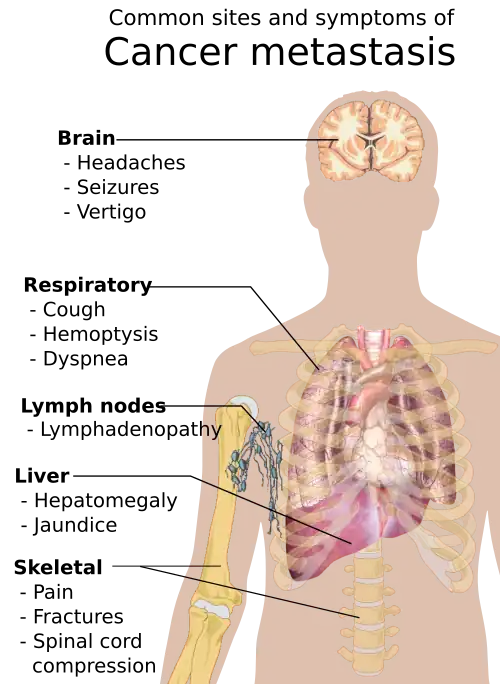

Metastasis is the spread of cancer to other locations in the body. The dispersed tumors are called metastatic tumors, while the original is called the primary tumor. Almost all cancers can metastasize.[40] Most cancer deaths are due to cancer that has metastasized.[41]

Metastasis is common in the late stages of cancer and it can occur via the blood or the lymphatic system or both. The typical steps in metastasis are:

Different types of cancers tend to metastasize to particular organs. Overall, the most common places for metastases to occur are the lungs, liver, brain, and the bones.[40]